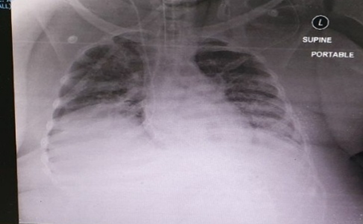

The physical examination of the patient showed that the woman has mild signs of respiratory distress. She had a body temperature of 37.6°C, blood pressure of 112/65 mmHg, pulse rate of 70 bpm, and respiratory rate of 15 bpm. She had oxygen saturation level of 94% on high flow nasal cannula. On the other hand, the laboratory investigations on admissions revealed that the patient had a lymphocyte count of 0.321×103/µL and white blood cell count of 2.50×103/µL. The laboratory test results also showed that the woman had a normal neutrophil count and coagulation profile. The patient had a BUN unit of 1.6 mmol/L, procalcitonin concentration of 0.05 ng/mL, creatinine level of 13 µmol/L, LDH of 338 µL, magnesium ion concentration of 0.73 mmol/L D-dimer concentration of 0.05 mg/L, sodium ion concentration of 135 mmol/L, and ferritin concentration of 310 ng/mL. Furthermore, the result of the venous blood gas analysis indicated the occurrence of metabolic acidosis that is characterized by a pH of 7.28, pCO2 of 63, pO2 76, PFR of 76, and HCO3 of 25. The result of the chest radiograph showed the presence of bilateral lung infiltrates suggesting ARDS (Figure 1).

Figure 1 Chest x-ray on admission showing bilateral basal consolidation with evolving ARDS.